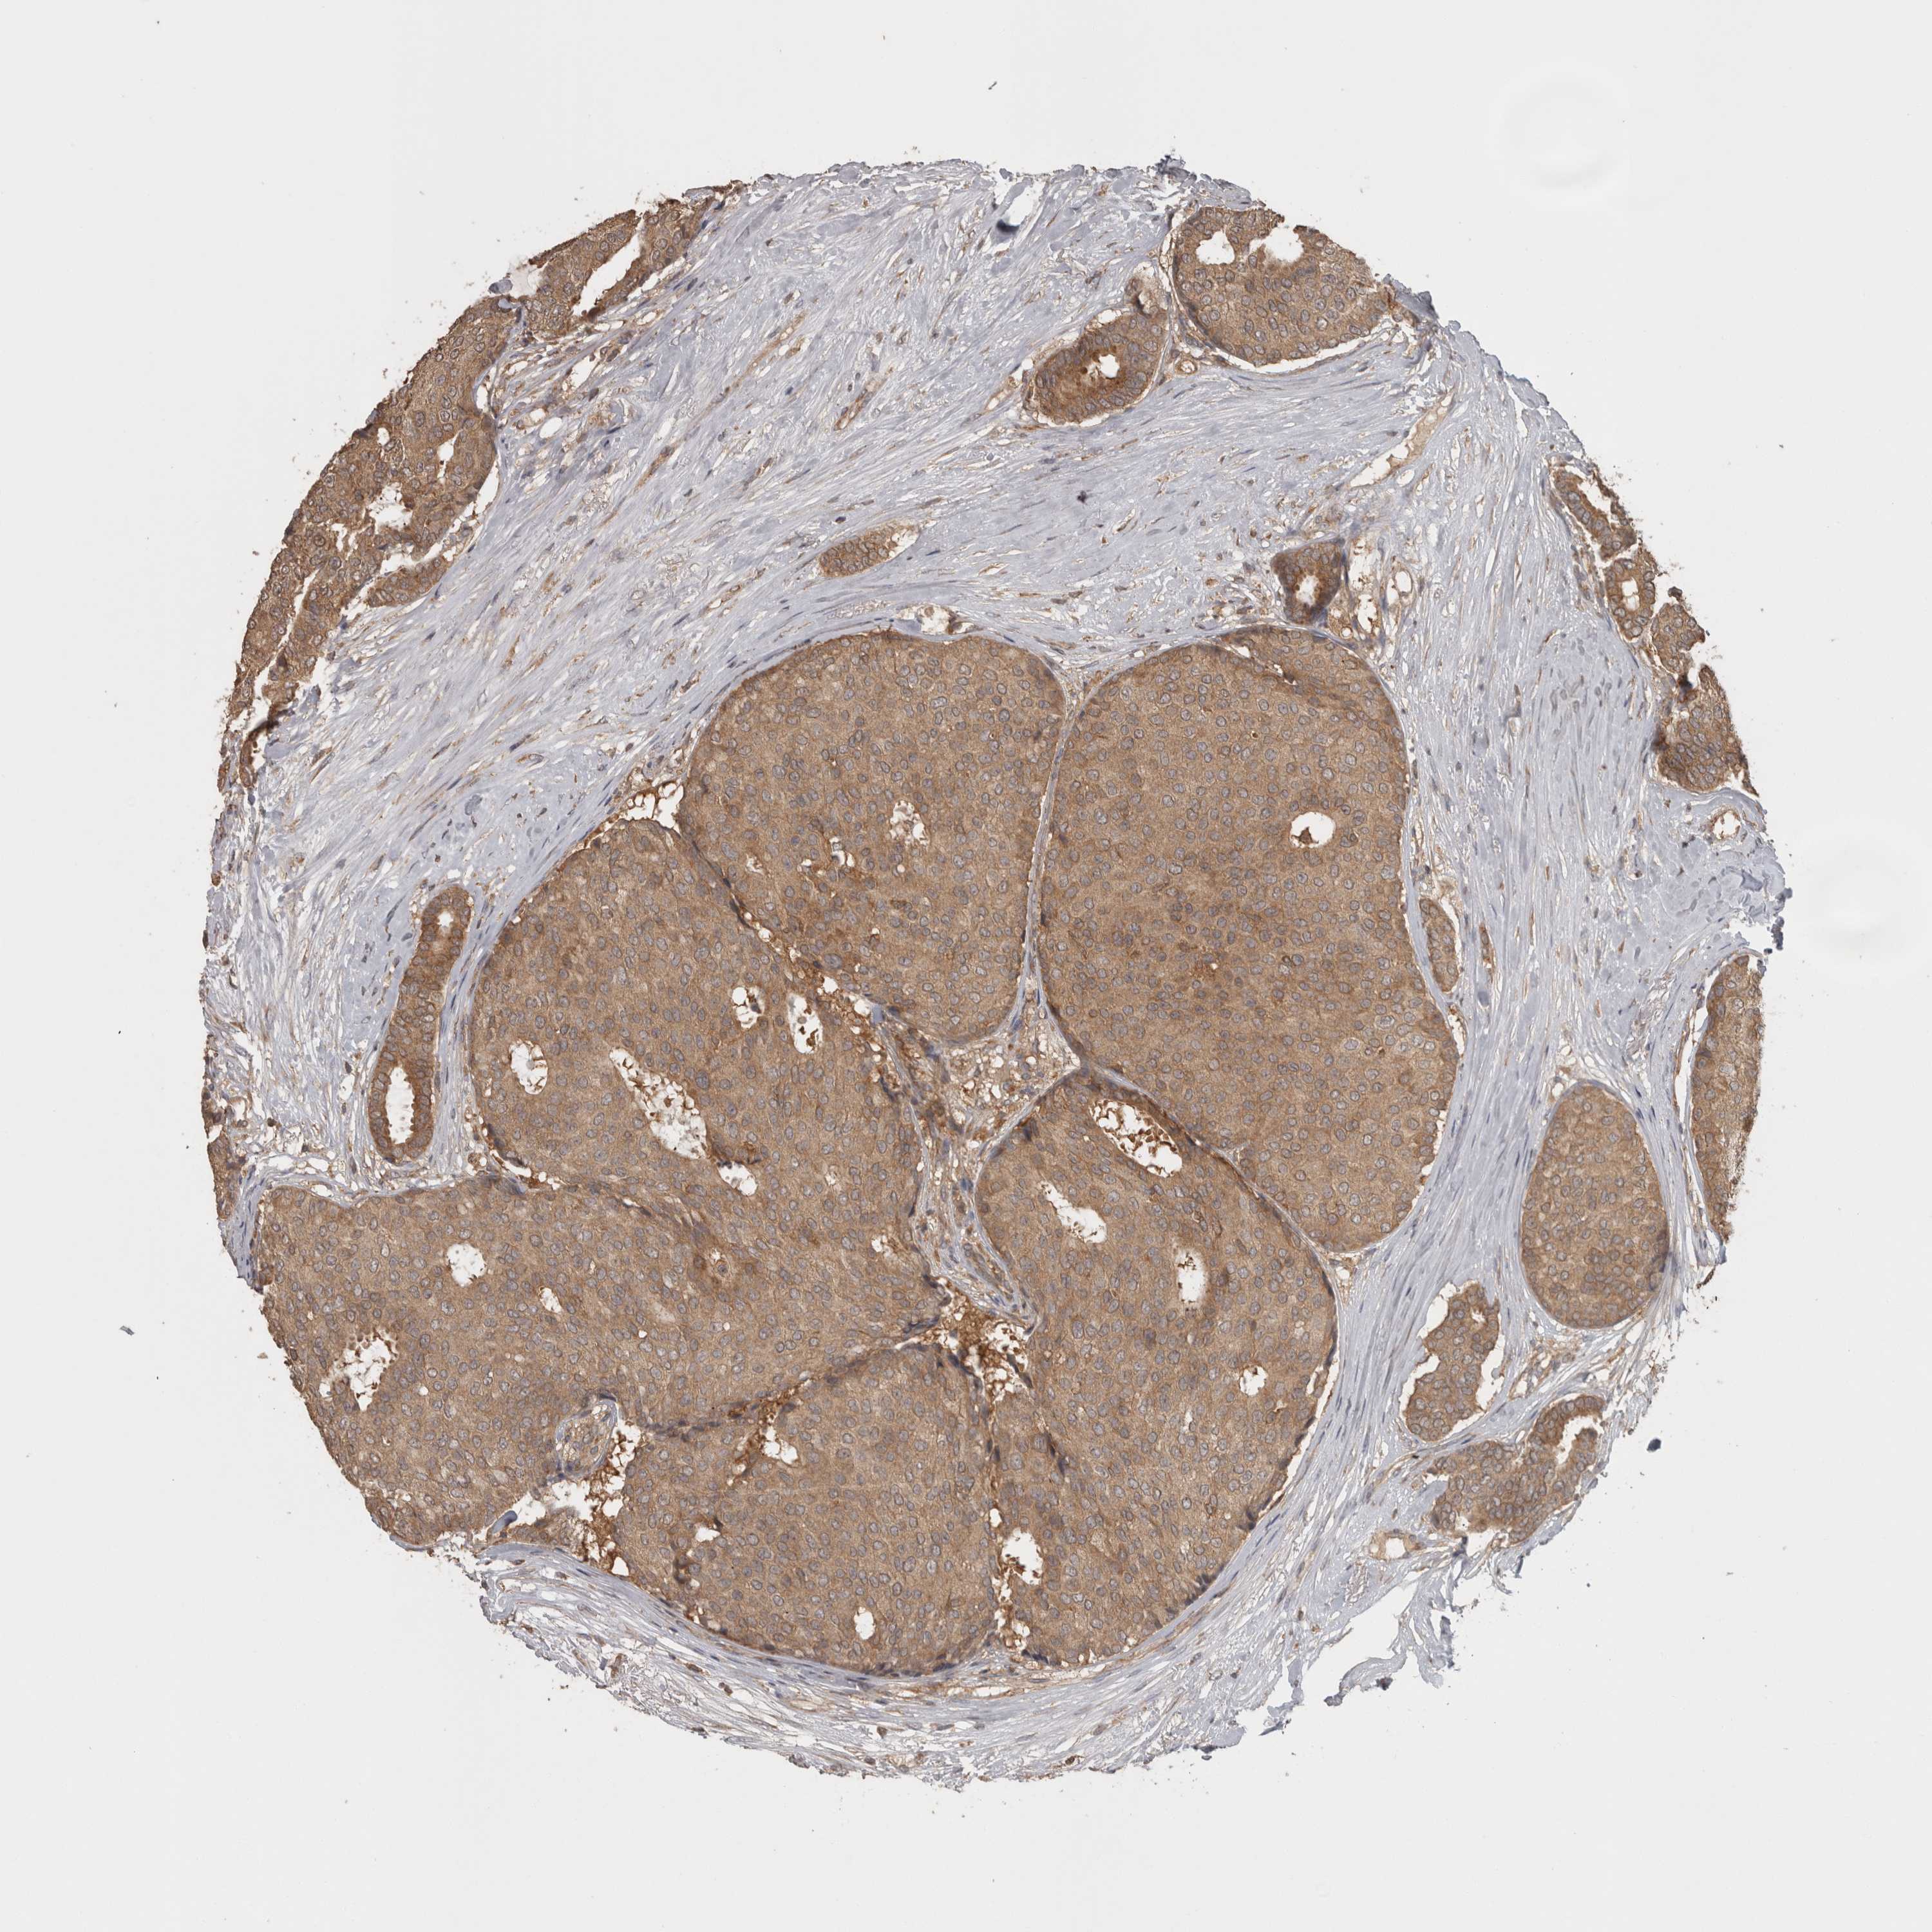

BRCA TCGA BRCA VALIDATION PROTEIN EXPRESSION

ANTIBODIES

AND

VALIDATION